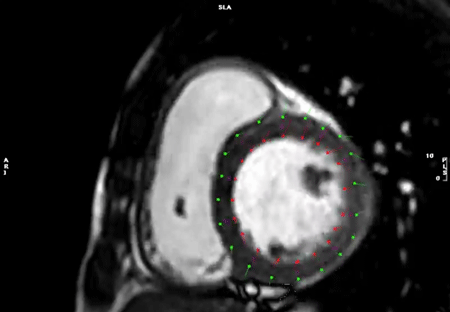

(1)strain(Figs. 11–13, Movies 2–5)

Pediatric Cardiology and Cardiac Surgery 40(4): 260-271 (2024)

Fig. 11 Left ventricular (LV) and right ventricular (RV) chamber quantification. For LV chamber quantification, the endocardial (red) and epicardial (green) contours are delineated in a stack of short axis slices and a 4 chamber long-axis. Counters should be marked in the round.

strainの解析結果・方法

左室全体としての心筋ストレインをglobal strainといい,それぞれの方向でglobal circumferential strain(GCS),global radial strain(GRS),global longitudinal strain(GLS)と呼ばれる.四空長軸像や左室二腔像,短軸像などの断面像を用いて以下の方法に則って心室strainの解析を行うと,GCS,GRS,GLSがそれぞれ算出される.また,これらの断面を複数組み合わせて同時に解析を行うことで3Dでのstrain解析を行うことが可能となり,AHA 16 segment modelでの結果表示や,心室3Dモデルにカラーを載せて結果を表示することも可能となる.一例として,解析アプリケーション“CVI42”(Circle Cardiovascular Imaging, Calgary, Canada)を用いた解析結果を示す(Figs. 12, 13, Movies 2–5).

一心周期内の任意の一時相で心内膜・心外膜をトレースするだけで,あとはアプリケーションが自動的に心筋の収縮・拡張を心周期全体で追跡し,strainが算出される.

この解析に際してのコツは2つあり,トレースの仕方と解析結果の確認である.

まず,心内膜・心外膜のトレース線は駆出率を算出した際のトレース線をそのまま用いることも可能である.しかし,乳頭筋や右室の索状組織などを心筋に含んだトレース線のままでは,心内膜線が複雑な凹凸を示すため,うまく心筋の収縮を追跡できないことが多い.このため,strainの計測をする際には心内膜のトレース線を,乳頭筋や右室の索状組織などを含ない凹凸のないシンプルな曲線(心腔容積計測では推奨されないトレース線)として描くことがコツである(Fig. 11).